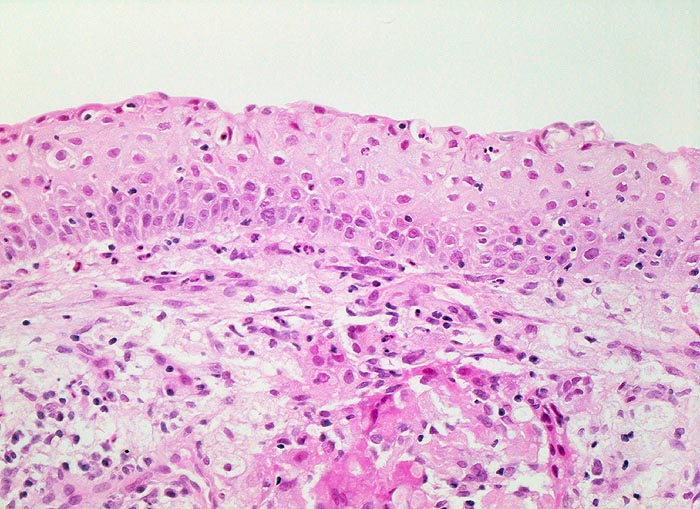

AP/ Plattenepithelmetaplasie der Bronchusschleimhaut

Plattenepithelmetaplasie der Bronchusschleimhaut

Metaplasie / Heterotopie

Lunge, Mediastinum mit Thymus

Lunge